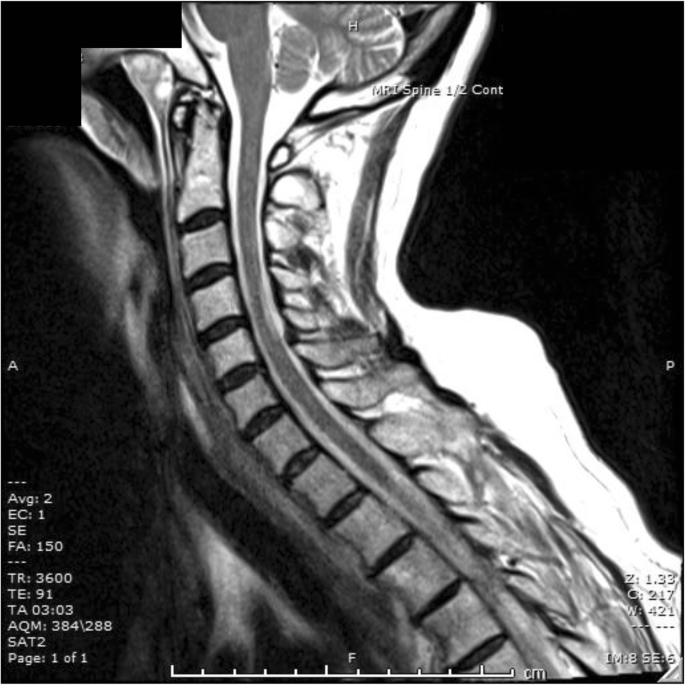

Cervical Spinal Cord Mri In A 49 Year Old Male Presenting With Subacute Download Scientific Diagram

www.researchgate.net